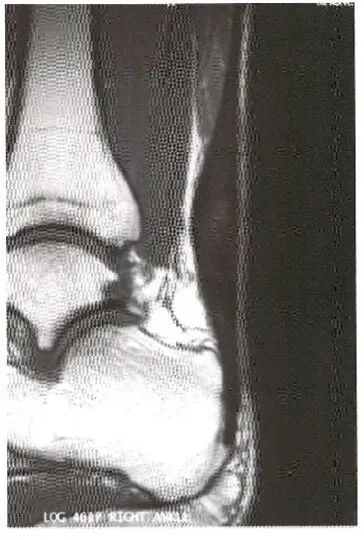

部分肌腱撕裂:  A,跟腱远端明显增厚,近端重度部分撕裂的部位明显变薄;B,脂肪抑制序列显示了肌腱断裂的程度。